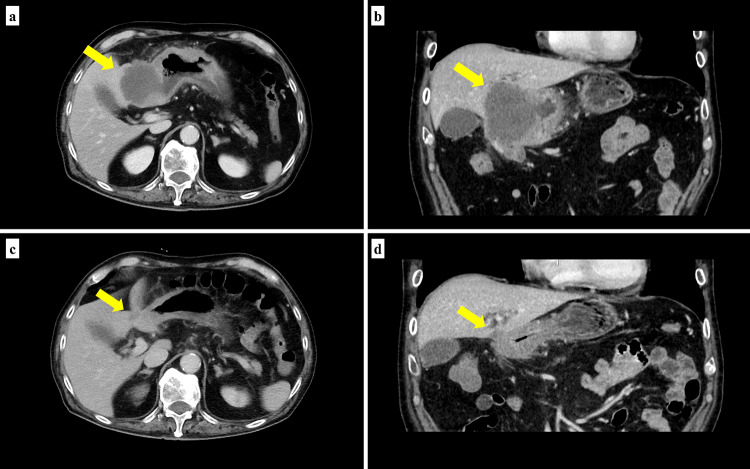

Chemotherapy for advanced gastric cancer has progressed significantly in the past few decades. Biomarker-specific drugs, including anti-human epidermal growth factor receptor 2 (HER2) drugs for HER2-positive patients and immune checkpoint inhibitors for those with microsatellite instability-high (MSI-H), have become common. However, patients who are positive for HER2 and have MSI-H are extremely rare, and there are no established treatments for these patients. We present the case of a 75-year-old, male patient with gastric cancer with lymph node metastases and liver infiltration. Biomarker analysis revealed HER2 3 + , loss of MLH1, and MSI-H. After three cycles of S-1, oxaliplatin, and trastuzumab, the primary tumor and metastases shrank markedly. He subsequently underwent gastrectomy and hepatectomy as conversion surgery, achieving a pathologically complete response. He has been recurrence-free for seven months postoperatively. The present case demonstrated the efficacy of trastuzumab-containing chemotherapy followed by conversion surgery in a patient with HER2-positive, MSI-H, advanced gastric cancer.